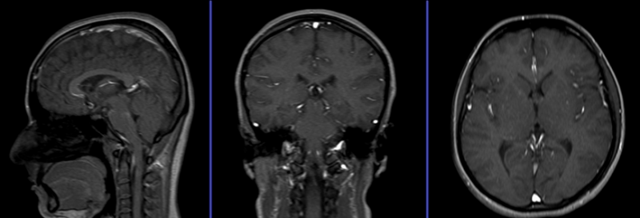

МРТ

Обе методики исследования характеризуются высоким показателем точности и эффективности, однако, каждая из них имеет ряд особенностей, которые принимаются во внимание при выборе конкретной процедуры.

МРТ сосудов отличается небольшим списком ограничений и безопасна для здоровья, т. к. чаще проводится без контрастирования. Этот метод диагностирования применим как для обследования сосудистой сетки, так и для элементов мягкой ткани.

Однако при черепно-мозговой травме МРТ с ангиографией эффективной мерой назвать нельзя. При подобных обстоятельствах необходимо найти трещины в черепной кости, сосудистые разрывы и сбои в работоспособности пищеварительной системы. МРТ сосудов не подходит для диагностирования костной и жидкостной структуры.